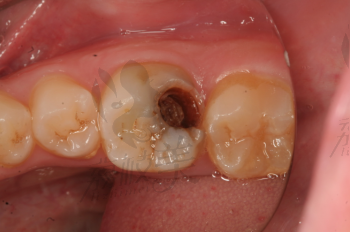

摘要:面對牙齒疼痛,特別是牙爛大窟窿帶來的困擾,需及時采取應對措施。建議盡快就醫(yī),進行專業(yè)牙齒檢查和治療。日常護理方面,注意口腔衛(wèi)生,定期刷牙,使用牙線和漱口水清潔口腔。飲食避免過冷過熱刺激,減少糖分攝入,以防細菌滋生。如需緩解暫時疼痛,可服用止痛藥,但不可長期依賴。預防牙爛,定期口腔檢查至關(guān)重要。

牙齒疼痛是常見的口腔問題之一,而牙爛了個大窟窿晚上痛更是讓人難以忍受,這種情況不僅影響生活質(zhì)量,還可能引發(fā)其他口腔疾病,本文將為您解析牙爛窟窿的原因,并探討應對方法和預防措施。

1、齲齒:齲齒是牙齒爛掉的主要原因之一,長期不注意口腔衛(wèi)生,細菌滋生導致牙齒逐漸腐蝕。